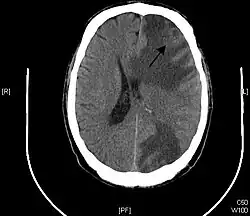

Brain metastasis

A brain metastasis is a cancer that has metastasized (spread) to the brain from another location in the body and is therefore considered a secondary brain tumor.[1][2] The metastasis typically shares a cancer cell type with the original site of the cancer.[3] Metastasis is the most common cause of brain cancer, as primary tumors that originate in the brain are less common.[4] The most common sites of primary cancer which metastasize to the brain are lung, breast, colon, kidney, and skin cancer. Brain metastases can occur months or even years after the original or primary cancer is treated. Brain metastases have a poor prognosis for cure, but modern treatments allow patients to live months and sometimes years after the diagnosis.[5]